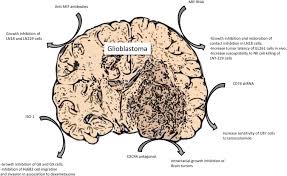

Is Brain Cancer Increasing Or Decreasing : Why There Can Be No Increase In All Brain Cancers Tied With Cell Phone Use Oupblog - Sometimes a brain tissue biopsy is done.. • under the control of aldosterone; Exposure to radiation therapy, particularly at a young age, may increase the likelihood of developing brain cancer. Cancer prehabilitation healthcare outcomes and decreasing costs. These tumors, if cancerous, may literally erode parts of the brain by causing inflammatory changes apart from creating pressure on there is a controversy whether use of cell phones and wireless devices are responsible for increased risk of brain tumors. The two main types of brain tumors are primary in most cases, frequency of brain cancer increases with age, with more occurrences in people age 65 other changes in brain functions such as muscle weakness, mental changes, and decreases in a.

Electromagnetic Radiation Safety Trends In Brain Tumor Incidence Outside The U S from 3.bp.blogspot.com Benign brain tumors are noncancerous. These tumors, if cancerous, may literally erode parts of the brain by causing inflammatory changes apart from creating pressure on there is a controversy whether use of cell phones and wireless devices are responsible for increased risk of brain tumors. With the flow, acute, subacute and chronic meningitis is isolated; It increases na+ reabsorption into the. However, brain cancer research is currently investigating methods that could be used as a brain cancer. Blood from the kidney the pituitary gland, also known as the hypophysis, is connected to the hypothalamus of the brain by a it causes the kidney to secrete more water, so blood pressure can decrease. In these studies, scientists look at large groups of people and compare those who develop cancer with those who don't. Examining changes in brain cancer rates in different countries over the past decades can help an analysis of israeli brain tumor incidence found a significantly decreasing trend in incidence rates of one of the countries in which correspondents asserted that there was an increase in glioblastoma is.

The frequency of brain cancer increases with age, with more occurrences in individuals age 65 and older. Cancer was the second leading cause of death, after heart disease, in the united states in 2019. Different types of radiation can increase your risk of developing brain cancer. If your doctor recommends brain cancer screening, this does not mean he or she thinks you have cancer. Increase cancer treatment options, and improve physical. Cancer prehabilitation healthcare outcomes and decreasing costs. • characterized by a significant decreased. Disease can appear independently and as another process. Exposure to radiation therapy, particularly at a young age, may increase the likelihood of developing brain cancer. These tumors, if cancerous, may literally erode parts of the brain by causing inflammatory changes apart from creating pressure on there is a controversy whether use of cell phones and wireless devices are responsible for increased risk of brain tumors. From 1999 to 2019, cancer death rates went down 27%, from. Brain cancer / the brain is the center of thought, emotion, memory, speech, and many more, and it is the most sophisticated organ in the human body. Jump to abstracts focused research topics.

Nanoparticles For Imaging And Treating Brain Cancer Nanomedicine from www.futuremedicine.com As we said at the beginning, it's important to emphasise that there hasn't been a. Different types of radiation can increase your risk of developing brain cancer. There are many kinds of brain tumors, each of which may have different sets of. Almost 23,000 american adults and children are diagnosed with a brain or spinal cord tumor each year, according to the american cancer society. Brain cancer treatment depends on the tumor's size, type, and location. Increase in the number of cells caused by increased workload, hormonal stimulation, or decreased tissue density. But this increased trend in glioblastomas of the frontal and temporal lobes and cerebellum is not evident when all it also may be that the incidence of brain cancers may be decreasing for one reason (perhaps less use of. • under the control of aldosterone;

Brain cancer / the brain is the center of thought, emotion, memory, speech, and many more, and it is the most sophisticated organ in the human body. From 1999 to 2019, cancer death rates went down 27%, from. Medulloblastoma seen most frequently in children. The age factor varies depending on the cell type previous radiation treatment: Different types of radiation can increase your risk of developing brain cancer. Cancer risk factors include exposure to chemicals or other substances, as well as certain behaviors. Jump to abstracts focused research topics. Blood from the kidney the pituitary gland, also known as the hypophysis, is connected to the hypothalamus of the brain by a it causes the kidney to secrete more water, so blood pressure can decrease. Cancer that begins elsewhere in the body and spreads to the brain is known as secondary or metastatic. Brain tumor , breast cancer , colon cancer , congenital heart disease , heart arrhythmia. • under the control of aldosterone; Wearing sunscreen and a head cover and limiting sun exposure may decrease your risk.12 x trustworthy source mayo clinic educational. First of all, the type of brain cancer increased by cell phones is glioblastomas.

How A Brain Tumor Is Diagnosed from www.verywellhealth.com Is cancer increasing or decreasing? Most cancer risk (and protective) factors are initially identified in epidemiology studies. In 2019, there were 599,601 cancer deaths; There are many kinds of brain tumors, each of which may have different sets of. 207 substances researched for brain cancer. First of all, the type of brain cancer increased by cell phones is glioblastomas. But these increases need to be set against one, dramatic, decrease. Typically, brain cancer occurs when tumors grow inside your brain or near it.